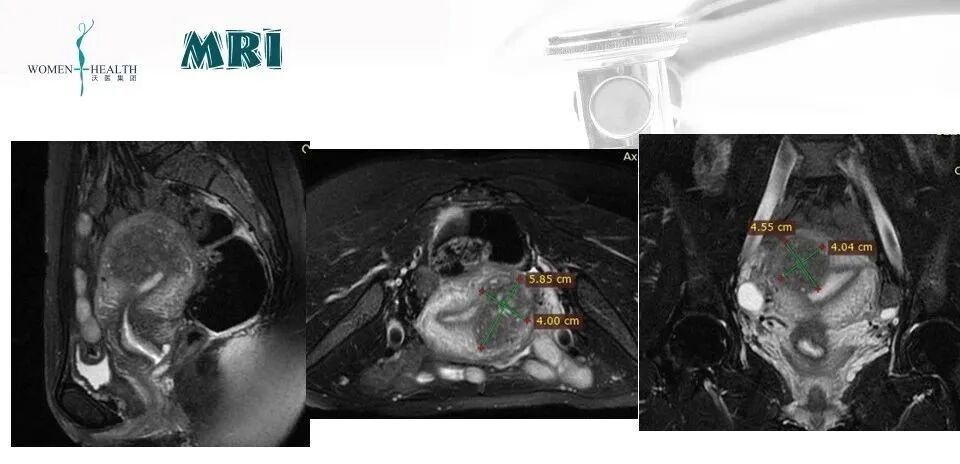

阴道超声(2023-2-11):子宫前壁欠均,局部39*29mmMRI提示宫底靠近前壁腺肌症病灶59*40*46mm